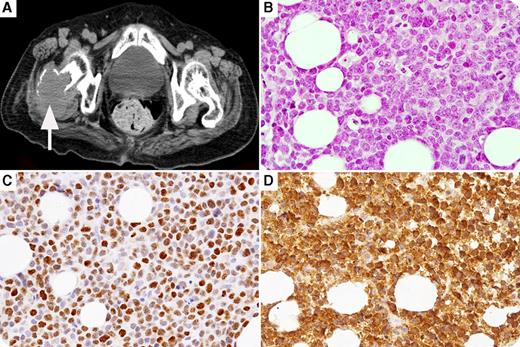

An 83-year-old woman was admitted for diplopia. She was initially diagnosed with cyclin D3–positive mantle cell lymphoma (MCL; which tested positive for CD5, CD20, and SOX11, but was negative for cyclin D1, cyclin D2, and 37% Ki-67 index) in the pterygopalatine fossa with a good response to radiation. She had a relapse in the pterygopalatine fossa and experienced bone lesions, including in the right femur (panel A, computed tomography scan), with drowsiness caused by hypercalcemia, 1 year later. Laboratory tests showed the following: albumin, 2.1 g/dL; calcium, 11.6 mg/dL; parathyroid hormone, 5 pg/mL; and parathyroid hormone–related protein (PTHrP), 3.9 pmol/L (normal, <1.1 pmol/L). Histological findings were consistent with transformation to the cyclin D3–positive blastoid variant of MCL (MCL-BV), retaining the same immunophenotype as initial diagnosis but with an increase in Ki-67 index to 93%. PTHrP expression was observed in lymphoma cells (panel B, hematoxylin and eosin, original magnification ×40; panel C, cyclin D3 immunostain, original magnification ×40; panel D, PTHrP immunostain, original magnification ×40).

A rare subtype of cyclin D1–negative MCL (positive for cyclin D2 or cyclin D3) was reported to be a part of the spectrum of MCL. MCL rarely transforms histologically into MCL-BV, which is more aggressive than typical MCL. Hypercalcemia may have been attributable to both PTHrP production by MCL-BV cells and local osteolytic metastases.